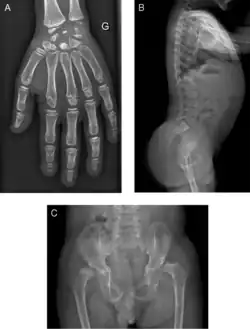

| Radiograph of a WRS child presenting with dysplastic bone growth in various regions of the body. | |

Initially, patients with neonatal or early-childhood onset diabetes are possible candidates for having Wolcott–Rallison syndrome.[1] The other features include multiple epiphyseal dysplasia, osteopenia, intellectual disability, and hepatic and renal dysfunction.[1] Patients having features that suggest Wolcott–Rallison syndrome can be referred for genetics testing. The key way to test for this disease is through genetic testing for EIKF2AK3 mutations.[7] Molecular genetic analysis can be done for the patient and the parents to test for inherited or de novo mutations. It can also show whether the patient's parents are heterozygotes or homozygotes for the normal genotype.[4] X-rays can show bone age in relation to actual age. In typical WRS patients the bone age is a few years less than the chronological age.[4][5][8][9] Hypothyroidism is rare in WRS patients but can occur.[4]